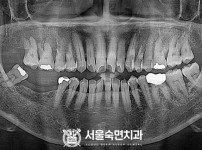

임플란트-전후사진4

임플란트-전후사진5

치과를-선택할-때-꼭-확인하세요-서울숙면치과-임플란트-전후사진